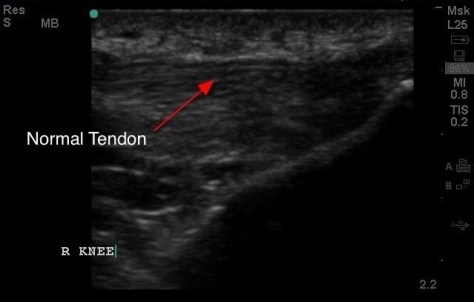

The Normal Tendon…..otherwise known as “The Ray of MSK”